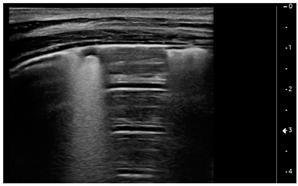

We used the following definitions to characterize the LUS patterns [15]:

- A-lines: normal appearance of horizontal, equidistant, parallel artefacts originating at regular intervals from the pleural line (visceral and parietal pleura)

- B-lines: laser-like signals arising from the hyper-echoic pleural line, extending to the bottom of the screen without fading and moving synchronously with respiration

- Subpleural consolidation: Small, triangular, or oval shaped, echo-poor region adjacent to the pleura without a tissue-like pattern (AB)

- Lobar consolidation: Large, hypoechogenic region adjacent to the pleura with a tissue-like pattern (AB) and an irregular pleural border

- Pleural effusion: Anechoic or hypoechoic collection external to lung parenchyma, typically in a dependent lung region with or without respiratory movement of the lung within the effusion (flapping lung)

Using the mentioned LUS semeiotics, lung aeration and lung pattern were classified following a 5 point score:

- Normal lung sliding, regular pleural line, and A lines

- Vertical artifacts, pleural line indented with several B-lines per field in the posterior regions

- Vertical artifacts, pleural line indented with several B-lines per field in all regions

- Broken pleural line with subpleural consolidations < 1 cm

- Consolidations > 1 cm with or without pleural effusion (Table 1).

Interestingly, the finding of subpleural and lobar consolidations with or without pleural effusion was associated with a lower LVEF on admission and need for inotrope use; also, presence of a LUS pattern of subpleural consolidations was associated with PICU length of stay.

Subpleural consolidations, on the other side, as well as lobar consolidations, have been described in viral pneumonitis and bronchiolitis, pneumonia, acute respiratory distress syndrome [24], and pulmonary infarction [25], but are not described in cardiogenic pulmonary edema [18].

Subpleural consolidations can also be present in a diffuse microembolic/microthrombotic event. This phenomenon is common in COVID-19 patients [27] because of thrombotic occlusion of small- to mid-sized pulmonary arteries with subsequent infarction of lung parenchyma and can show at LUS a triangular hypoechoic consolidation with sharp margins in the absence of air bronchograms [28].

Our patients showed the presence of subpleural consolidations or consolidations with or without pleural effusion correlating with the degree of heart failure (LVEF at admission and need for inotropes), and this is a new finding. Subpleural consolidations are common in COVID-19 pneumonia in children [8] and have also been described in asymptomatic pediatric patients [30,31]. It is possible that this pattern in MIS-C patients refers to sequelae of the primary infection that had not been detected during initial SARS-CoV-2 infection but was still present at time of MIS-C diagnosis. It is also possible that they are expressions of the inflammatory state that these patients show through fever and elevated markers of inflammation [32]. The correlation of subpleural consolidations with PICU length of stay could also be interpreted under this light as a sign of a more severe disease. MIS-C is a novel entity that follows the primary infection with COVID-19 in children which is still under investigation under different aspects. The inflammatory state in this disease seems caused from a cytokine storm that causes fever, elevation of all markers of inflammation and multiorgan failure, with activation of T cells, macrophages, natural killer cells and overproduction of immune or non-immune defense cells, and the release inflammatory cytokines and chemical mediators. Endothelial cell dysfunction follows, resulting in damage to the microvascular system and abnormal activation of the coagulation system, resulting in systemic small vessel vasculitis and extensive microthrombosis [33]. Therefore, it is possible to speculate that the pattern we found on LUS is a possible expression of a mix of pathological events on the lung parenchyma, a consequence of both the cardiogenic edema and a direct inflammatory/micro-embolic lung disease.